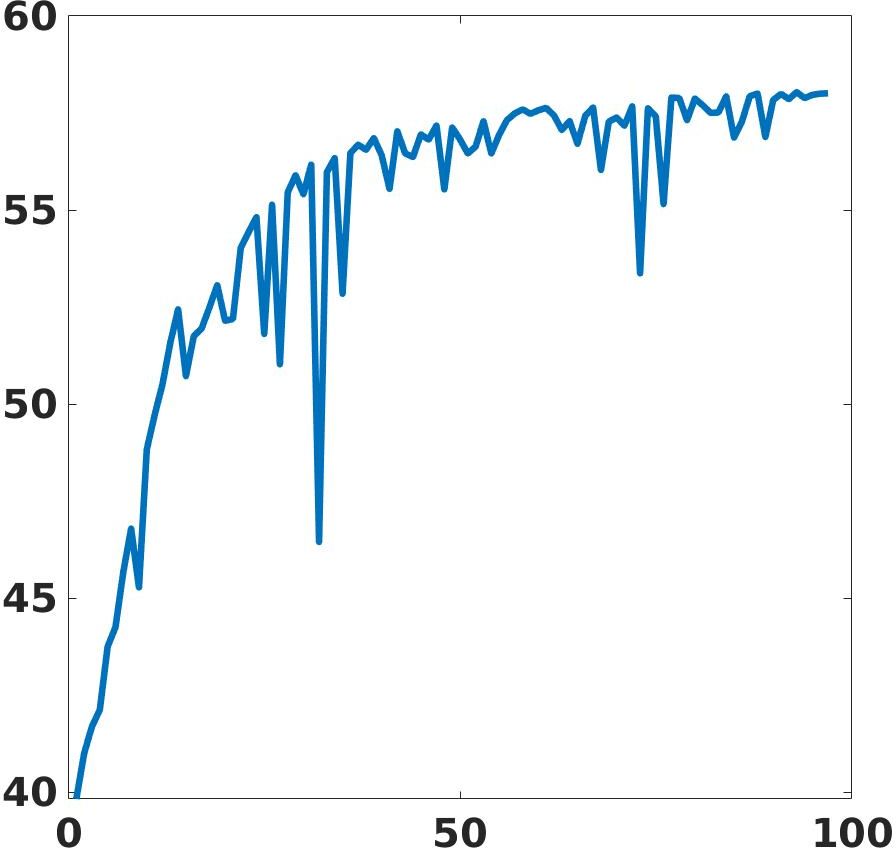

We define an HPC implementation of the proposed framework on the CINECA-Marconi100 cluster, exploiting both CPUs (IBM POWER9 AC922) and GPUs (NVIDIA Volta V100). We design a parallel and distributed implementation in TensorFlow2, and we train multiple networks with large data sets for the target medical application. To test the training phase of the learning-based networks in the HPC environment, we exploit 8 nodes, each one composed of 32 cores and 4 accelerators, for a theoretical computational performance of 260 TFLOPS, and 220 GB of memory per node. The parallel implementation of the deep learning framework and the high hardware performance reduce the computation time of the training phase by at least 100 orders less than a serial implementation on a standard workstation. Fig. 19 shows the training loss and validation PSNR. Both metrics show convergence property within 100 epochs iteration. In particular, the validation PSNR goes from a value of 41 to a value of 58 after 100 epochs.